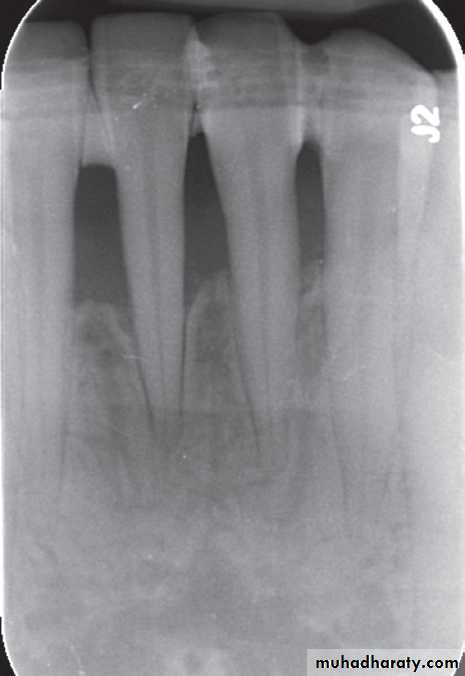

Postoperative radiograph of anterior mandible in localized aggressive periodontitis patient treated with a combination of antibiotic therapy, scaling and root planing, and surgical intervention.